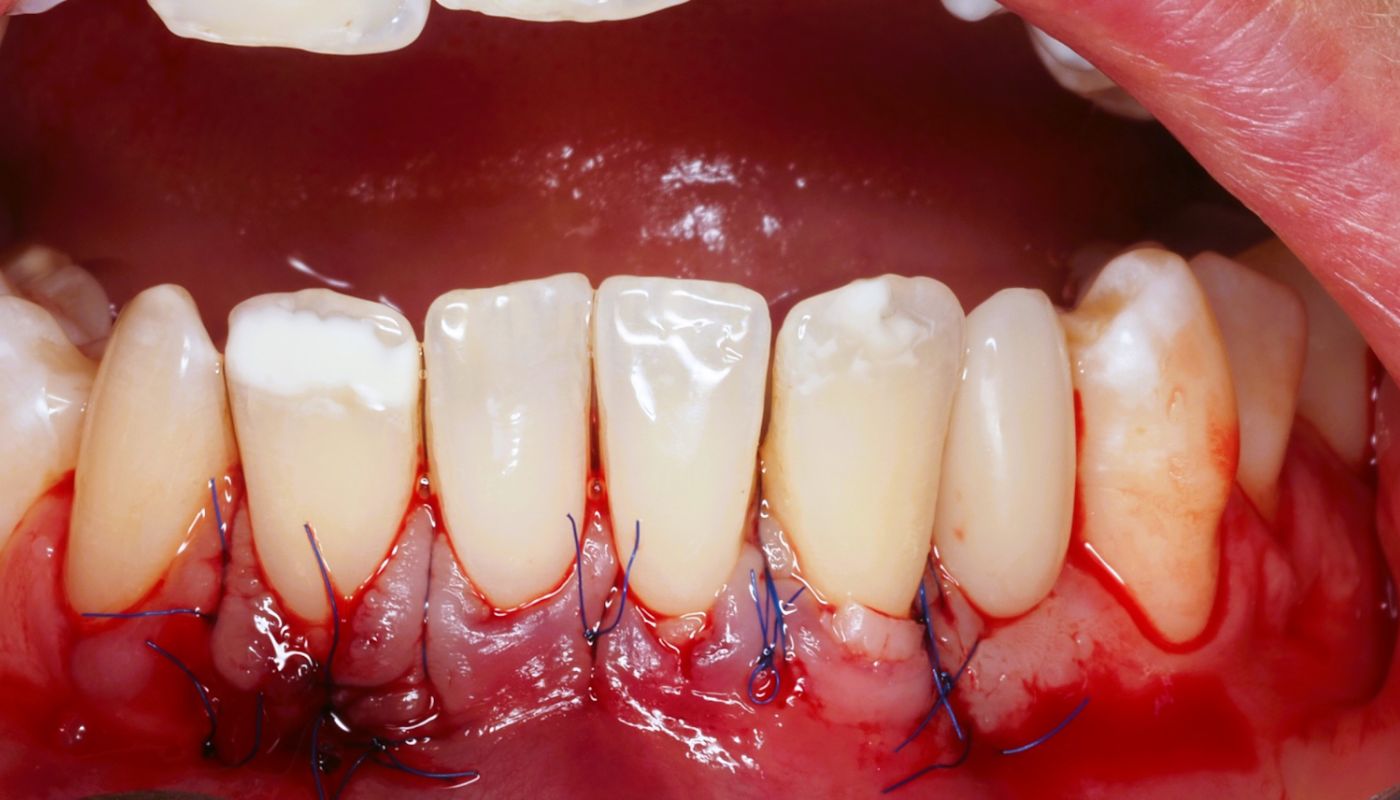

Najczęściej wykonywaną procedurą podczas leczenia widocznych szyjek jest chirurgiczne pokrycie części korzenia za pomocą autogennej tkanki, którą pobiera się z podniebienia. Metoda ta najczęściej jest wykonywana w periodontologii i jak dotąd tego typu leczenie przynosi najlepsze rezultaty.

Przeczep tkanek poprawia ogólną estetykę linii uśmiechu jak również wpływa na zminimalizowanie nadwrażliwości. Zdarza się, że metoda ta wykorzystywana jest po leczeniu ortodontycznym lub w trakcie, głównie u pacjentów z cienkim fenotypem dziąsła.

Zabieg polega na usunięciu kamienia podziąsłowego, z wykorzystaniem specjalnych narzędzi zwanych kiretami. Podczas zabiegu lekarz usuwa kamień nazębny, następnie poleruje powierzchnie korzenia oraz szyjki zębowej, nie naruszając przy tym reszty zęba. Czynnością kończącą zabieg jest nałożenie specjalnego preparatu z fluorem, którego zadaniem jest zamknięcie kanalików zębiny.

Działanie to ma głównie na celu zniwelowanie nadwrażliwości, która mogłaby pojawić się u pacjenta po oczyszczeniu zębów ze złogów kamienia. W przypadku pacjentów, gdzie nastąpiło duże skumulowanie się kamienia nazębnego, wszelkiego rodzaju zabiegi, jak np. przeszczep tkanek, zawsze muszą być poprzedzone wykonaniem kiretażu!